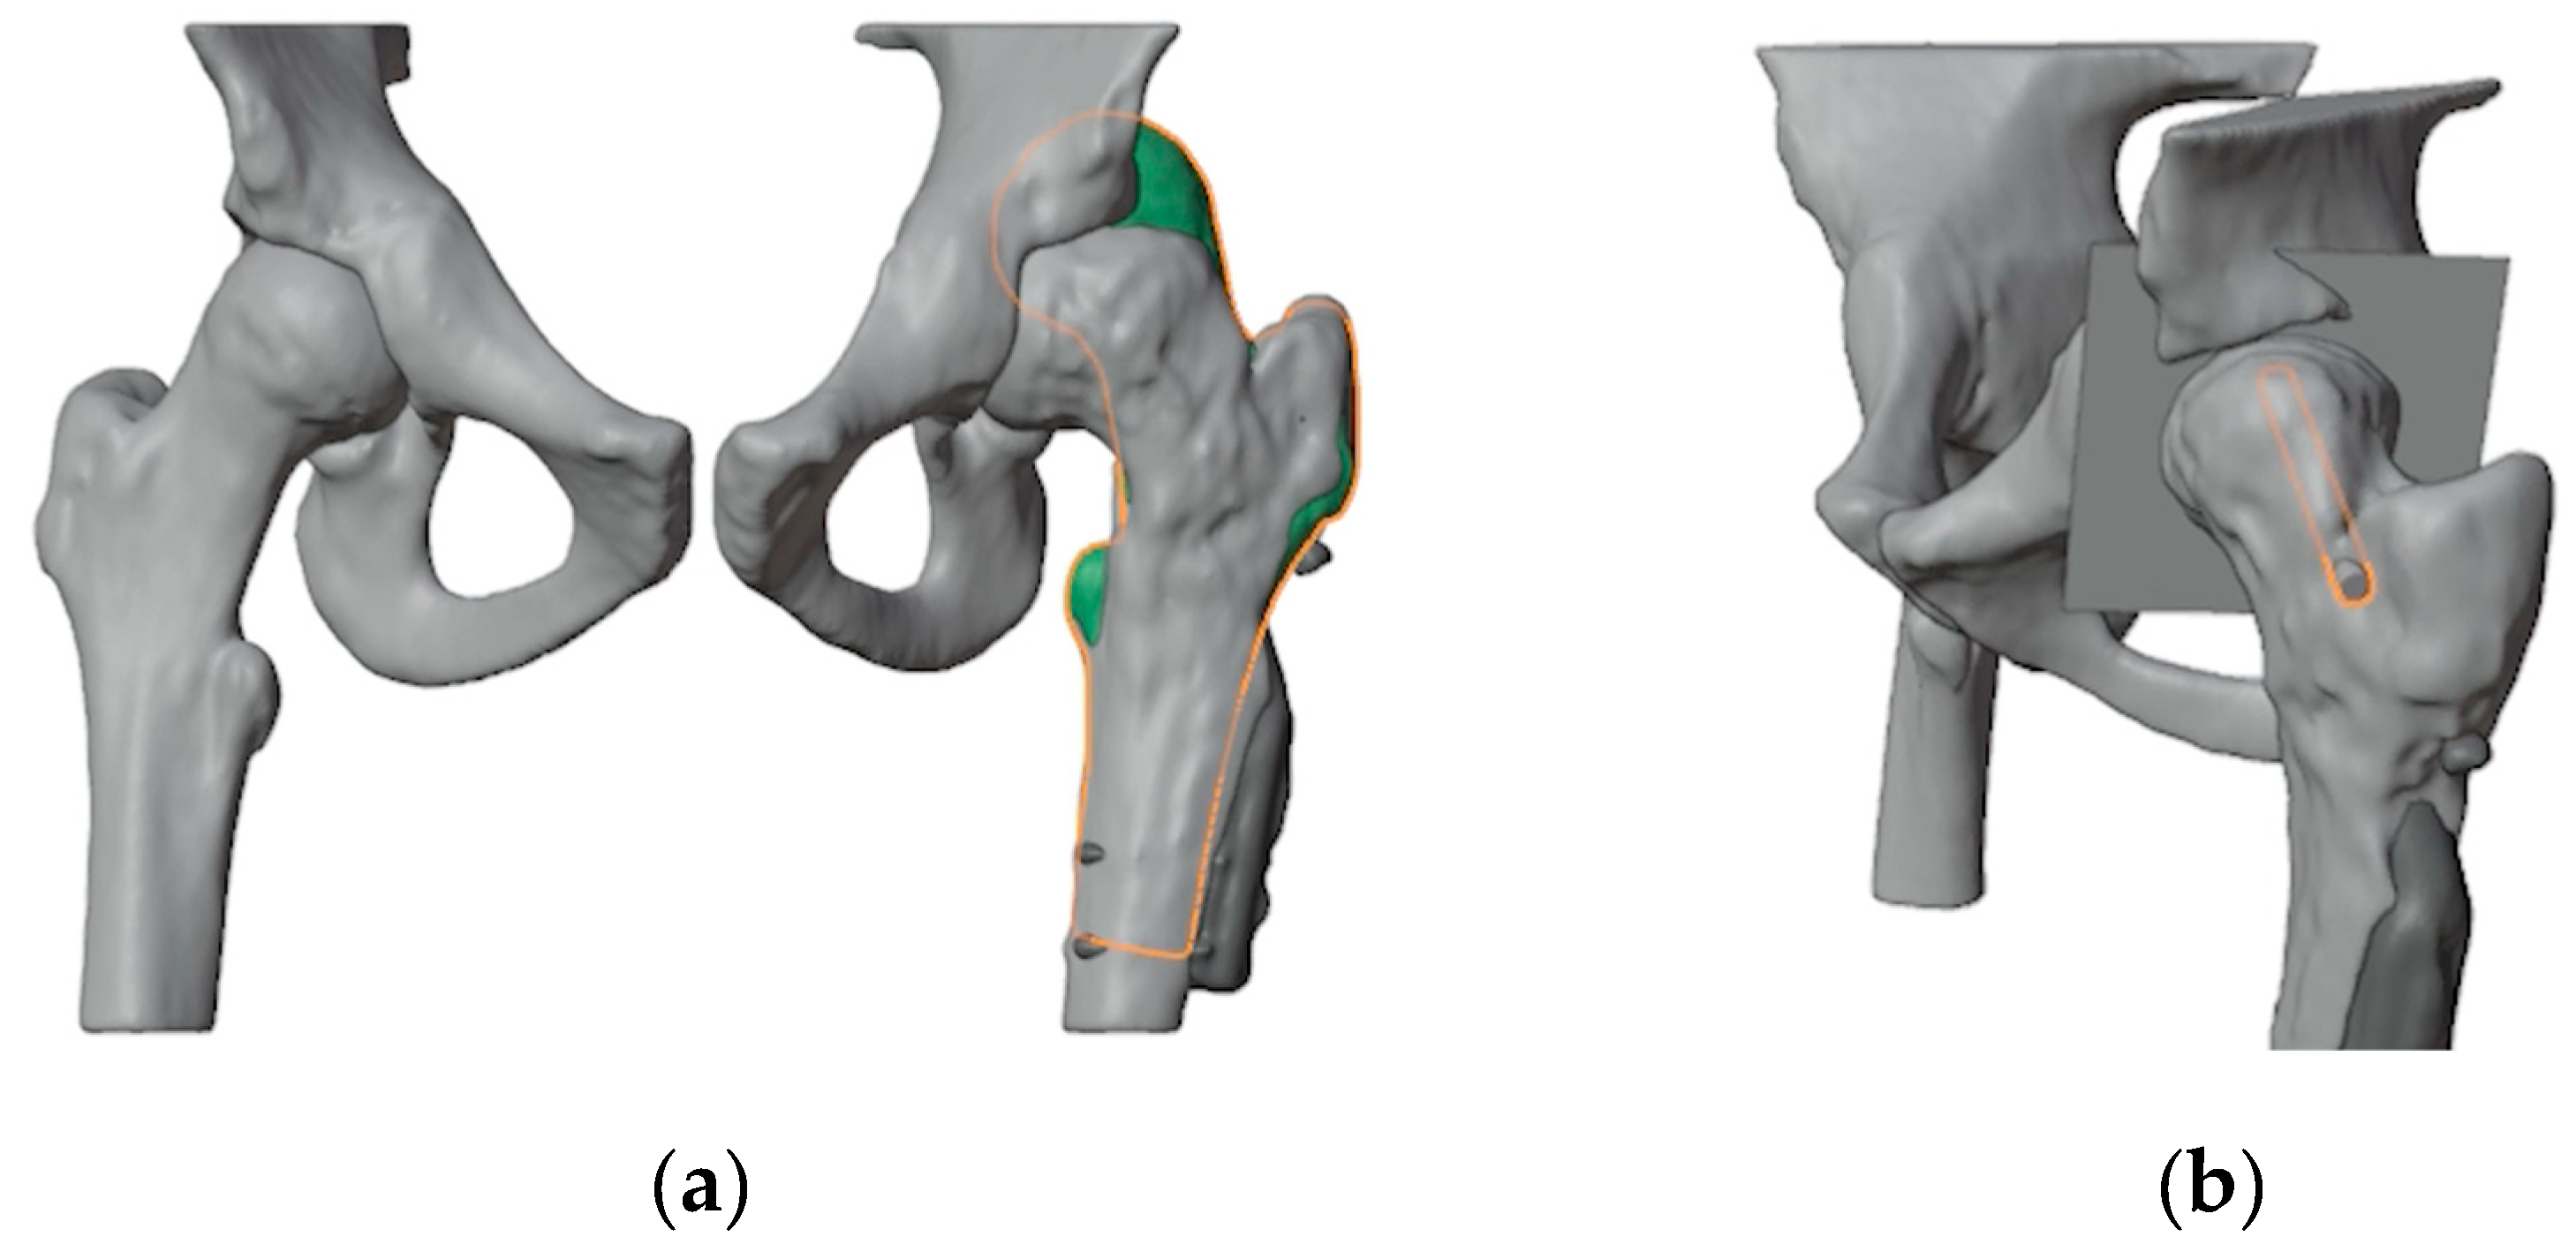

2.2. Virtual Surgical Planning and Design of 3D Printed Cutting Guide

The first step involved generating a virtual 3D model of the affected bone segments, derived from CT imaging using the hospital’s 3D-printing facility. The procedure and workflow, using Mimics Medical software (Materialise, Leuven, Belgium), have been previously described [11]. A mirrored model of the healthy contralateral hip was used to facilitate the analysis of the deformity (Figure 2a). A plane tangent to the base of the epyphysis was created in order to identify the best position of the screw for ISF. This process determined the precise entry point, direction, and length of the screw (Figure 2b). A 6.5 mm Rondò screw (Citieffe s.r.l., Calderara di Reno, Bologna, Italy) was chosen and its length was also determined.

Figure 2. (a) Overlap of the healthy contralateral femur; (b) Identification of a plane tangent to the base of the slipped epyphysis and of the position of the screw for ISF.